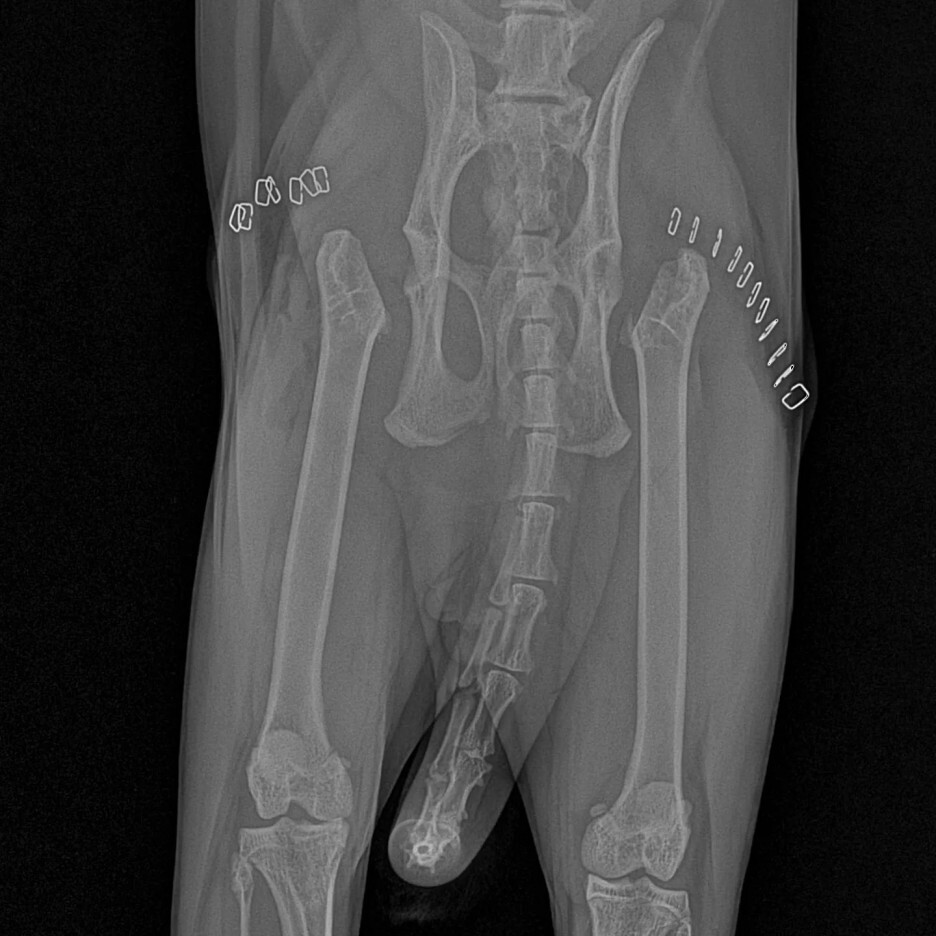

위에 있는 사진처럼 대퇴골두를 절단하는 방법!!

여기를 절단하면나중에 근육들이 생겨나면서 뼈와뼈를 잡아주어 근육이 골두의 역할을

하기 때문에 괜찮다고 합니다.

다른 방법은

골두를 살리면서 핀을 박는 겁니다.

그러면 본인의 대퇴골두는 유지가 되는거죠..

단점은 핀이 부러지거나끊어지게 되면 2차 3차 손상이 우려된다는 점.

그리고 나중에 빼야 하고 교체도 해야 하고 너무 번거롭고 장점보다 단점이많은 방법이었습니다.

그래서 대퇴골두 절골 수술을 하기로 결정했습니다.